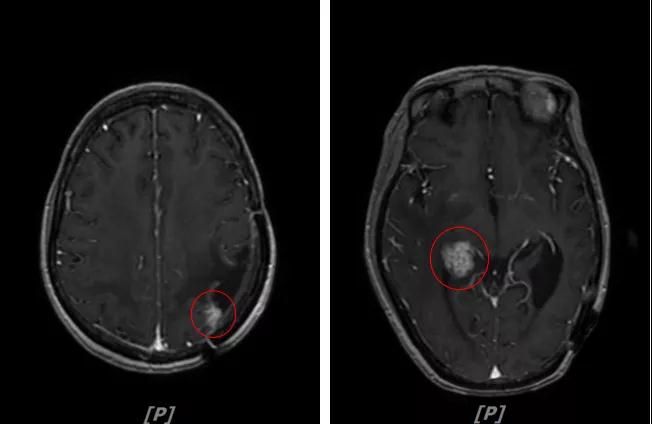

b.2014年3月全脑放疗结束后,予以LX方案治疗(拉帕替尼 1250mg qd+卡培他滨 1500mg bid)。每3个月规律复查,未见明显异常。下图为2014年6月患者行头颅增强MR检查,提示左顶叶脑转移瘤术后改变。

头颅增强MR:左侧顶枕叶见片状T1WI低信号、T2WI高信号影,增强后病灶边缘见局部斑片状强化改变,邻近脑膜轻度强化改变;右侧脑室三角区内侧见大小约8x14mm的结节影,T1WI低信号、T2WI等高信号,增强明显强化,灶周水肿明显;两侧脑室旁见片状异常信号,T1WI低信号,T2WI高信号,增强未见明显强化,余脑室、脑池、脑沟大小形态可,中线结构居中无移位

左顶叶脑转移瘤术后放疗后,左顶叶术区边缘强化灶;考虑肿瘤复发

右侧脑室三角区内侧转移瘤

两侧脑室旁云絮状异常信号,考虑放疗后改变

患者一线治疗的PFS为37个月。2017年1月,患者二线治疗为在原“拉帕替尼+阿那曲唑”基础上,加曲妥珠单抗治疗。患者头痛症状有所改善,病灶缩小,继续定期复查。